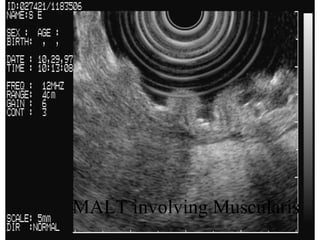

MALTOMA in stomach:

MALTOMA in stomach: MALT involving Muscularis